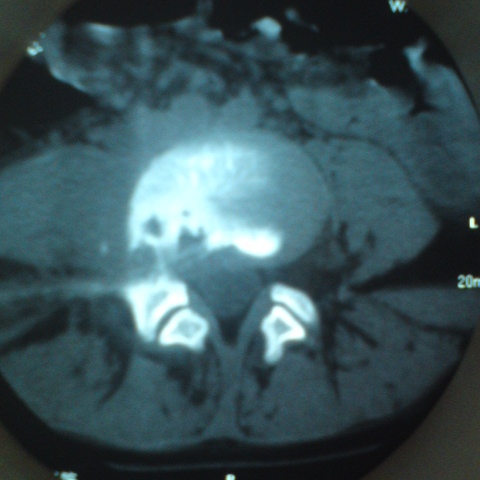

标题: CT27836:女 ,13岁,腰痛数月,加重一月,检查下腰部明显压 [打印本页]

标题: CT27836:女 ,13岁,腰痛数月,加重一月,检查下腰部明显压

考虑腰4椎体结核伴右侧椎旁及椎管右侧硬脊膜外脓肿形成。

骨质破坏+脓肿=结核

化脓性间盘炎症也有可能。

考虑腰椎结核伴右侧椎旁及椎管右侧硬脊膜外寒性脓肿形成;建议必要时行mri检查。